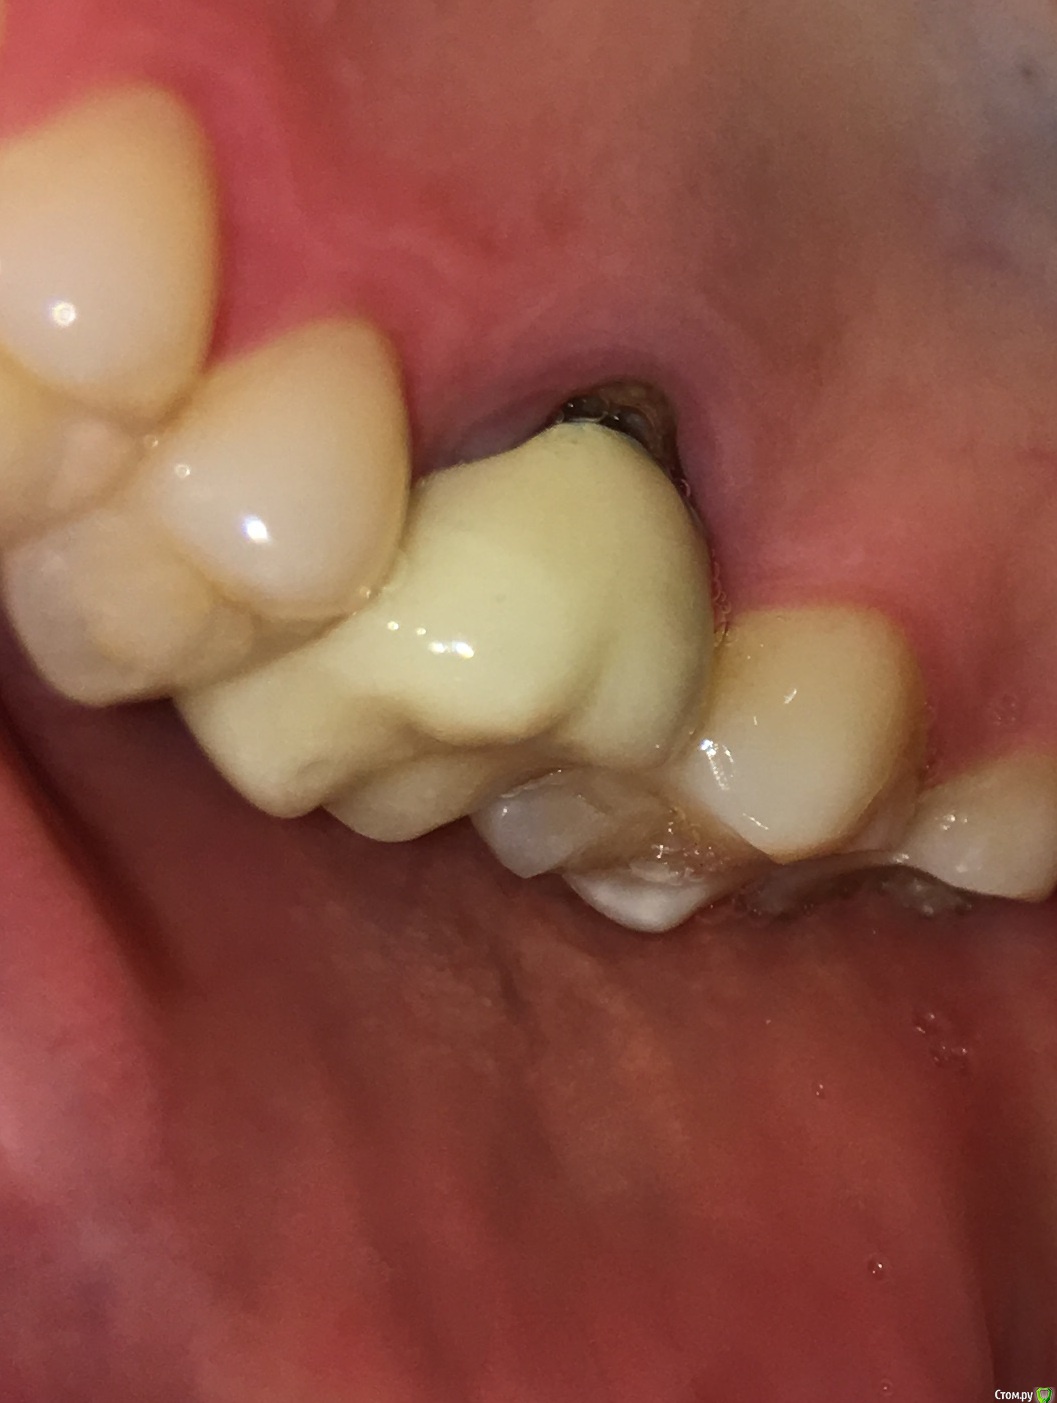

MichaelV Опубликовано 9 октября, 2019 Поделиться Опубликовано 9 октября, 2019 (изменено) Прошу подсказать специалистов.Несколько месяцев назад на 16-ый зуб поставили вкладку (однокоренную) и сделали коронку. Коронка стояла на временном цементе, сейчас отвалилась и надо идти ставить на постоянку. Решил внимательно рассмотреть, как она стоит. С внешней стороны особых вопросов нет - по десне идет тонка темная полоска на стыке коронки и вкладки. С внутренней стороны есть заметная щель. Посмотрите, пожалуйста, фото - нормально ли это или все-таки так быть не должно?Спасибо!(доп. информация - мне 36, нерв был удален лет 15-20 назад, 2 года назад перепломбировал каналы, но вкладку поставил только в этом году. Рад буду услышать рекомендации и советы по продлению жизни зуба в свете текущей ситуации). Изменено 9 октября, 2019 пользователем MichaelV Ссылка на комментарий

chervoncevdaniil Опубликовано 9 октября, 2019 Поделиться Опубликовано 9 октября, 2019 Честно говоря довольно странное решение для одиночной коронки в боковом отделе,это инициатива доктора или ваша была?По теме,может конечно вы ее не до конца одели или временный цемент немного завышает,а на постоянном будет все ОК,но судя по этому фото не совсем точно прилегает коронка Ссылка на комментарий

MichaelV Опубликовано 9 октября, 2019 Автор Поделиться Опубликовано 9 октября, 2019 Скорей всего моя (Семь раз отмерь - один раз отрежь), я всегда настороженно и внимательно отношусь к необратимым вещам, и если можно лишний раз проверить и подстраховаться - лучше так и сделать. Или я в этом случае заблуждаюсь? Тут второй вопрос у меня - насколько реально такую коронку, установленную на постоянный цемент, потом снять и заменить на другую?С внешней сотроны зазор минимальный, как раз м.б. на завышение временного цемента. Такой зазор с внутренней стороны - это очевидный брак, требующей переделки? Ссылка на комментарий